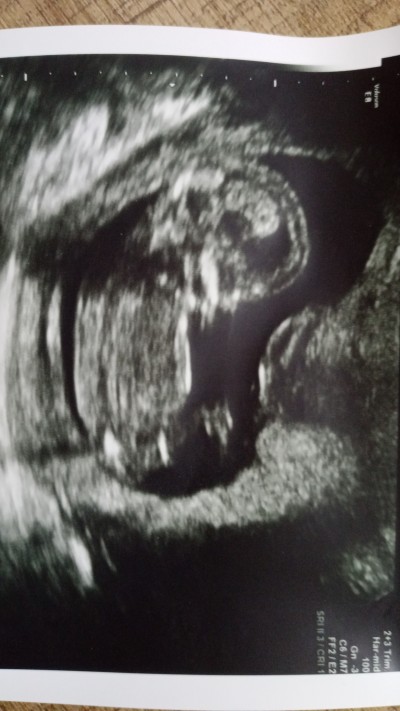

Sizce cinsiyeti nedir 14+3 oldu hala doktor söylemedi

image

Rabbim saglikli sahatli kavuşmayı nasip etsin inşallah canım bana kız gibi geldi

Tabi ki Dr değilim ben ki Dr lar bile 17 den önce tahmin bile yapmıyorlar.ben kuyruk sokumu tarafından bakıyorum.kizin daha düz oluyor oğlan daha yay gibi duruyor.ha dediğim gibi dr degilim

Kızdır bu öğrenince mutlaka yaz kesin kız kızımın ultrason resmiyle bire bi

Dr tahminde bulunmadı mı canım valla kız yazasım geldi erkek bebekte ultrason çene sivri olur oğlumun ultrason resminden biliyom bu kızımınkiyle aynı yinede takdiri ilahi sağlıklı olsun yeter:)

Erkeğe benziyor dedi sadece

Kız bebek canım kızımın ultrason una benziyor